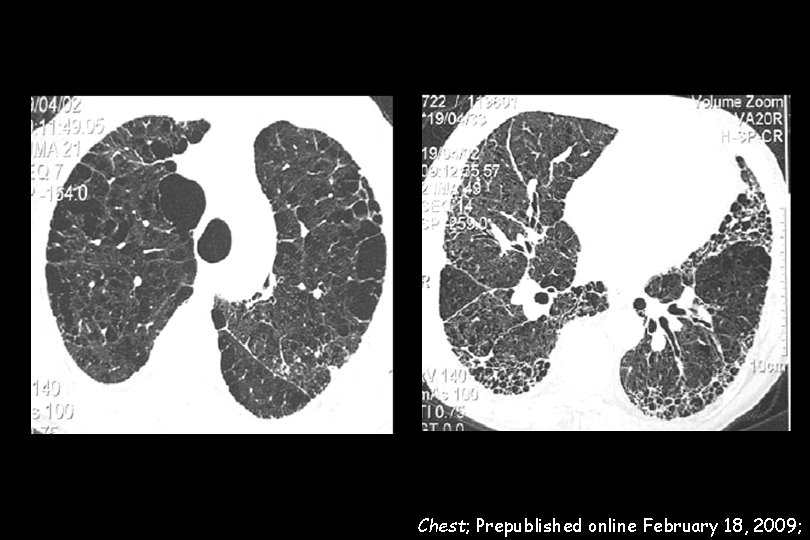

110 IPF patients wer evaluated. The prevalence of emphysema in the IPF cohort was 28% Pulmonary arterial hypertension (PAH) was evaluated with TTE and defined by an e. SPAP > 45 mm. Hg All IPF patients with emphysema showed PAH IPF with emphysema was highly associated with severe PAH (e. SPAP: 82. 3 ± 20. 2 mm. Hg versus 56. 7± 15. 3 mm. Hg, p < 0. 0001).

Chest; Prepublished online February 18, 2009;

e. SPAP (mm. Hg) 56. 7 ― 15. 3 e. SPAP (mm. Hg) 82. 3 ― 20. 2 Chest; Prepublished online February 18, 2009;